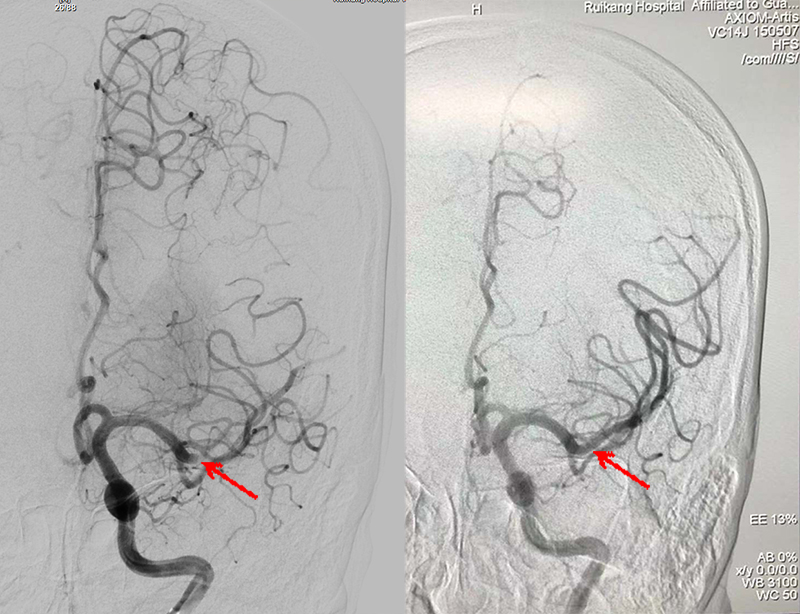

术前(左)术后(右)对比

在医务部的统筹安排下,脑病科介入团队、医学影像科、检验科、介入中心、手术麻醉科多学科通力协作,无缝衔接。静脉泵入尿激酶的同时,急查患者头颈部CTA提示左侧大脑中动脉M1段急性闭塞!脑病科一区的罗宁主任、脑病科二区张永全主任、方兴副主任认为有动脉取栓的适应症,并与患者家属充分沟通病情后一致决定,行急诊脑动脉取栓术,开通血管,与时间赛跑!手术由罗宁主任和傅有学主治医师操作。手术过程中,医院唐友明院长也第一时间赶到现场指导。经过团队1个小时的努力,脑动脉取栓术顺利完成,潘爷爷闭塞的血管实现了再通,终于转危为安。目前,在中西医结合术后康复作用下,潘爷爷的病情已经明显好转,右侧上、下肢均可自由抬起,精神矍铄。

脑动脉取栓术:是治疗急性缺血性脑卒中治疗最先进的技术,是将一种新型的支架取栓装置送入脑部血管,到达发病部位,用支架抓住血栓,可以直接取出大脑血管中阻塞血管的血栓,使血管迅速再开通,挽救患者脑组织,显著提高闭塞血管再通率,大大降低患者的死亡率及致残率。